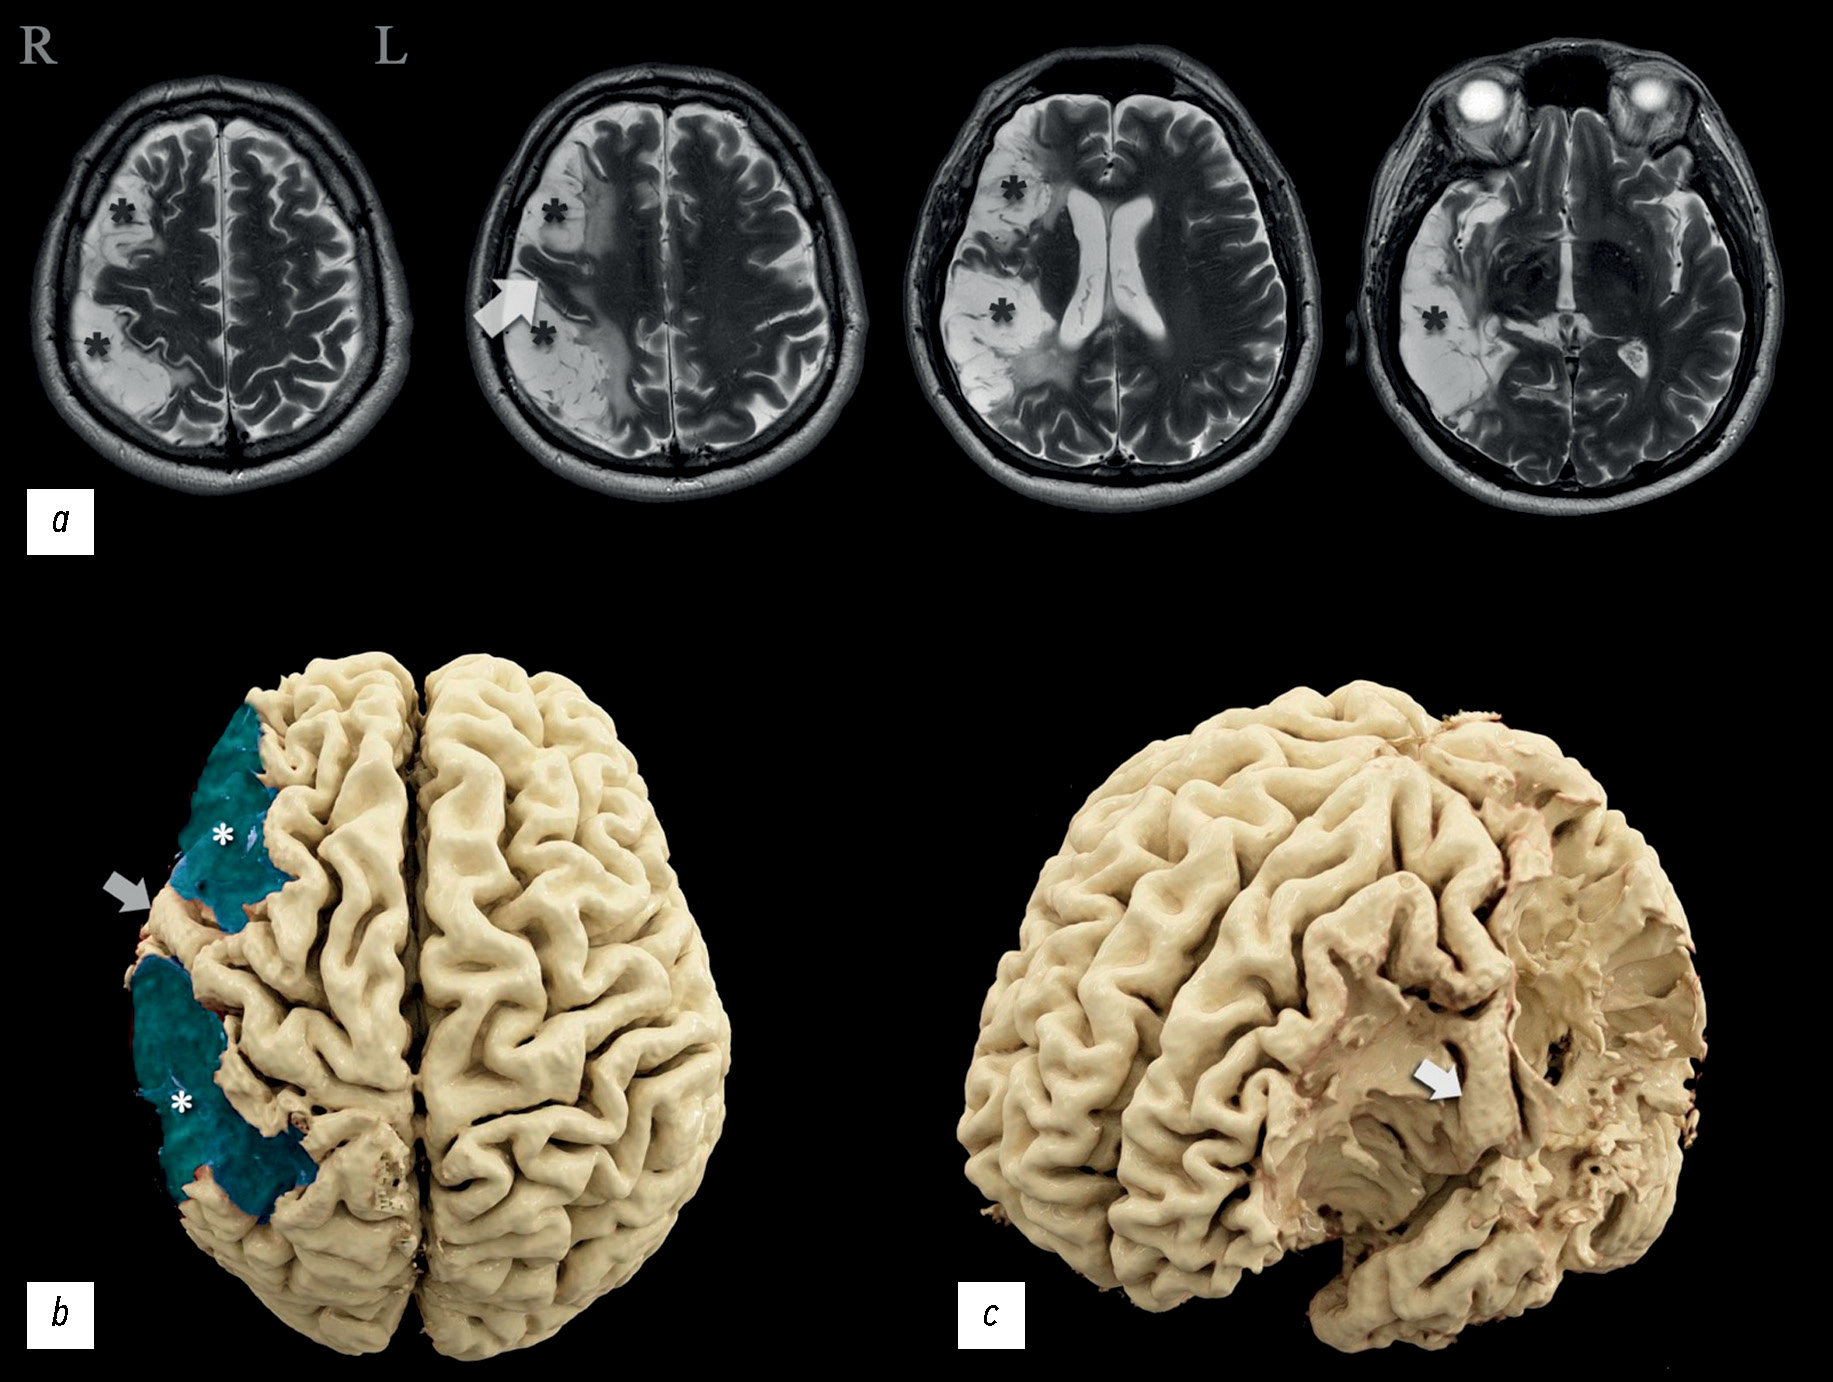

在临床病例分析中,一名患者在两次缺血性脑卒中后入院接受康复治疗,神经科医生和神经心理学家对其进行了检查,并通过脑电图、核磁共振成像、灌注评估计算机断层扫描、核磁共振纤维束成像和功能性核磁共振成像进行了全面的仪器检查。患者左侧肢体轻微瘫痪,自主活动调节能力障碍,神经动态指数轻度下降,注意力轻度下降,对自己的病情持批评态度。神经影像学检查结果发现,大脑中动脉区域的右侧次优势大脑半球存在广泛的梗塞后损伤。

显示脑损伤量与临床表现严重程度之间的失衡,并分析造成失衡的可能原因。根据功能研究的数据,确定优势半球,并提出功能中心重组的可能变体。与类似临床病例进行比较,分析其与本文的关系。所获得的信息扩展着运动执行、语言功能和运算能力主题改变区的认识。